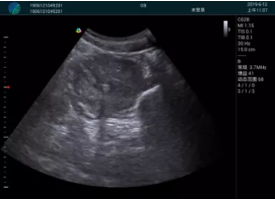

清晰顯示孕囊,通過(guò)軟件包計(jì)算孕齡7w+6d

M20實(shí)時(shí)引導(dǎo),術(shù)中清晰顯示孕囊被破壞和抽吸針的過(guò)程,清晰顯示吸引針

抽吸結(jié)束后縱切子宮,孕囊已被完全抽吸,未見(jiàn)明顯殘留

橫切子宮,發(fā)現(xiàn)右側(cè)宮腔靠近宮角處有少許脫模樣殘留

M20引導(dǎo)下,抽吸針找到右側(cè)宮角處再次清掃

二次抽吸后再次進(jìn)行超聲檢查,宮腔未見(jiàn)殘留,宮腔線清晰顯示